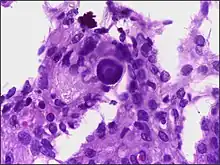

- A woven architectural pattern

- Psammoma bodies (spheroid calcifications)

- Syncytial cells (having indistinct cell membranes) with eosinophilic (pink) cytoplasms

- Round uniform nuclei

- Whorls (concentric cell arrangements)[15]

Histologically, meningioma cells are relatively uniform, with a tendency to encircle one another, forming whorls and psammoma bodies (laminated calcific concretions).[18] As such, they also have a tendency to calcify and are highly vascularized.